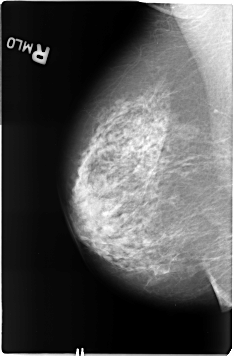

B_3361_1.RIGHT_MLO

RIGHT_CC LINES 4632 PIXELS_PER_LINE 3064 BITS_PER_PIXEL 12 RESOLUTION 50 NON_OVERLAY

RIGHT_MLO LINES 4624 PIXELS_PER_LINE 3032 BITS_PER_PIXEL 12 RESOLUTION 50 NON_OVERLAY